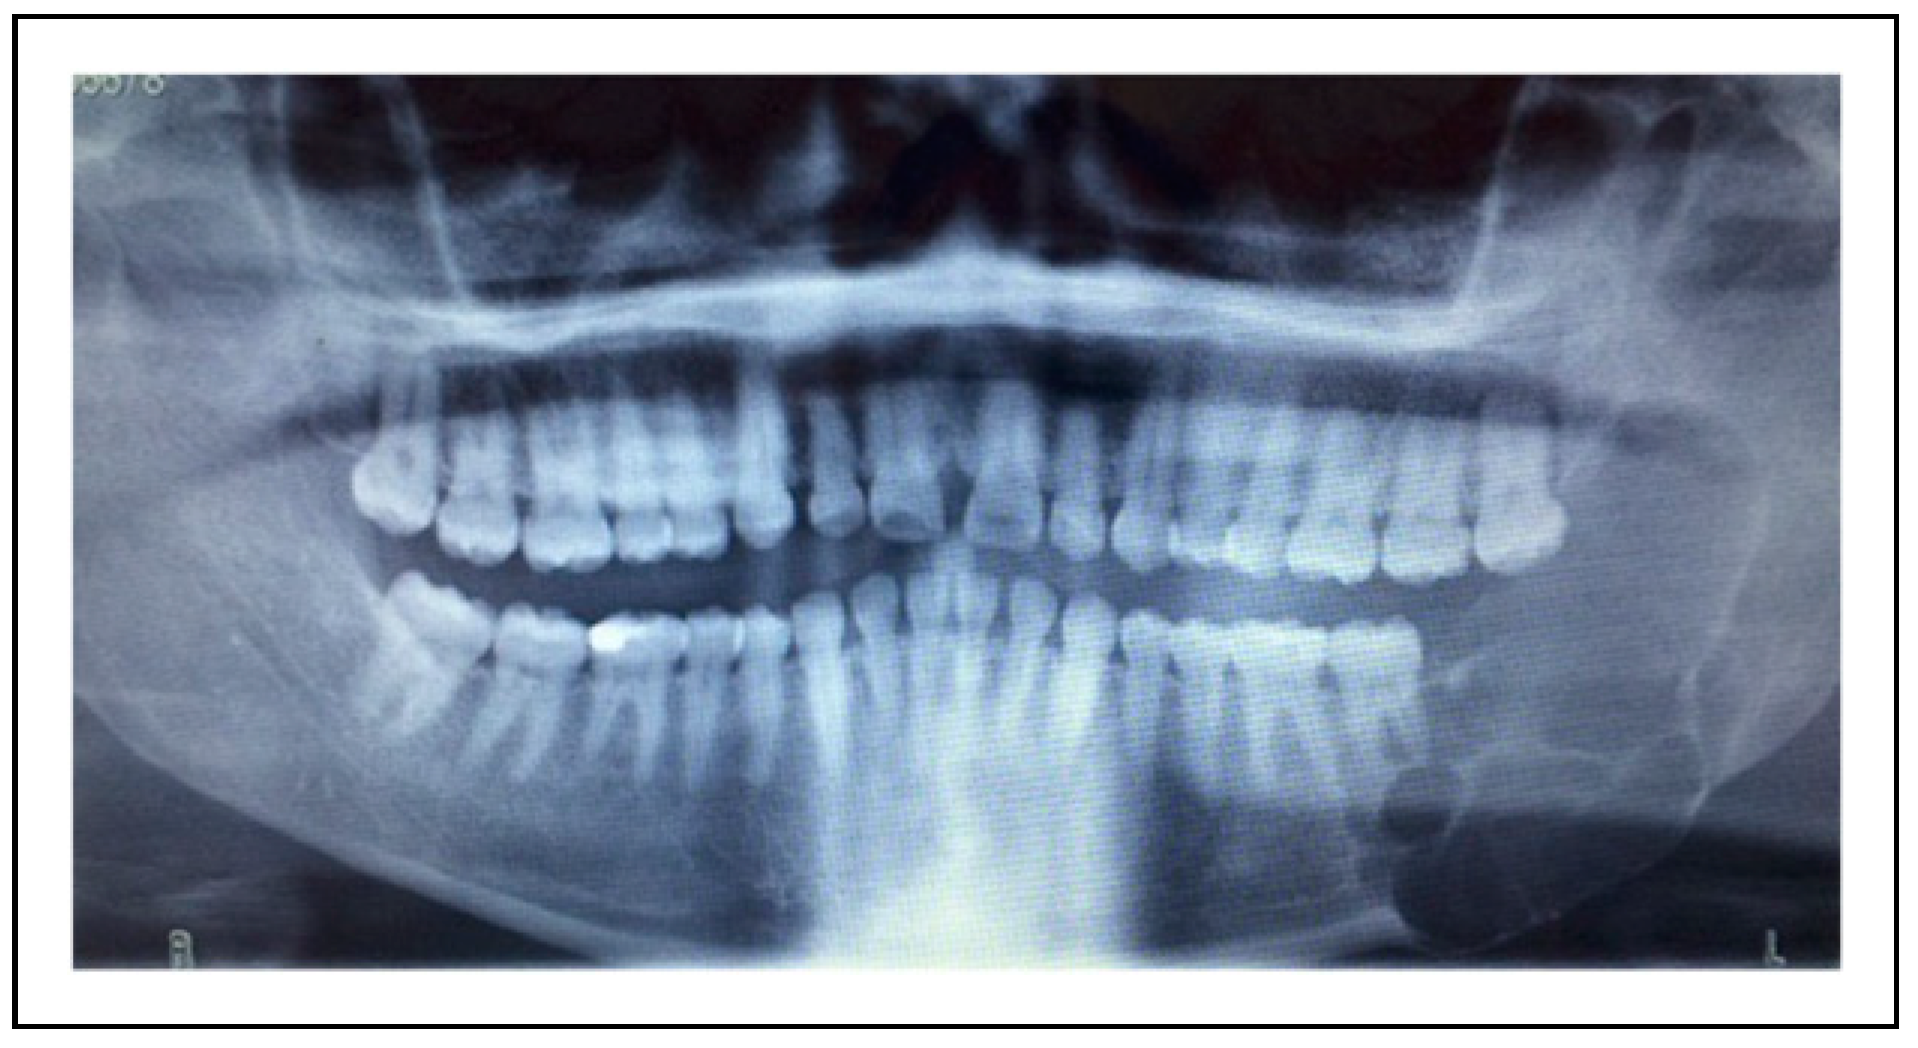

Bilateral TMJ Replacement With Complete Replacement of the Mandible, Patient 8